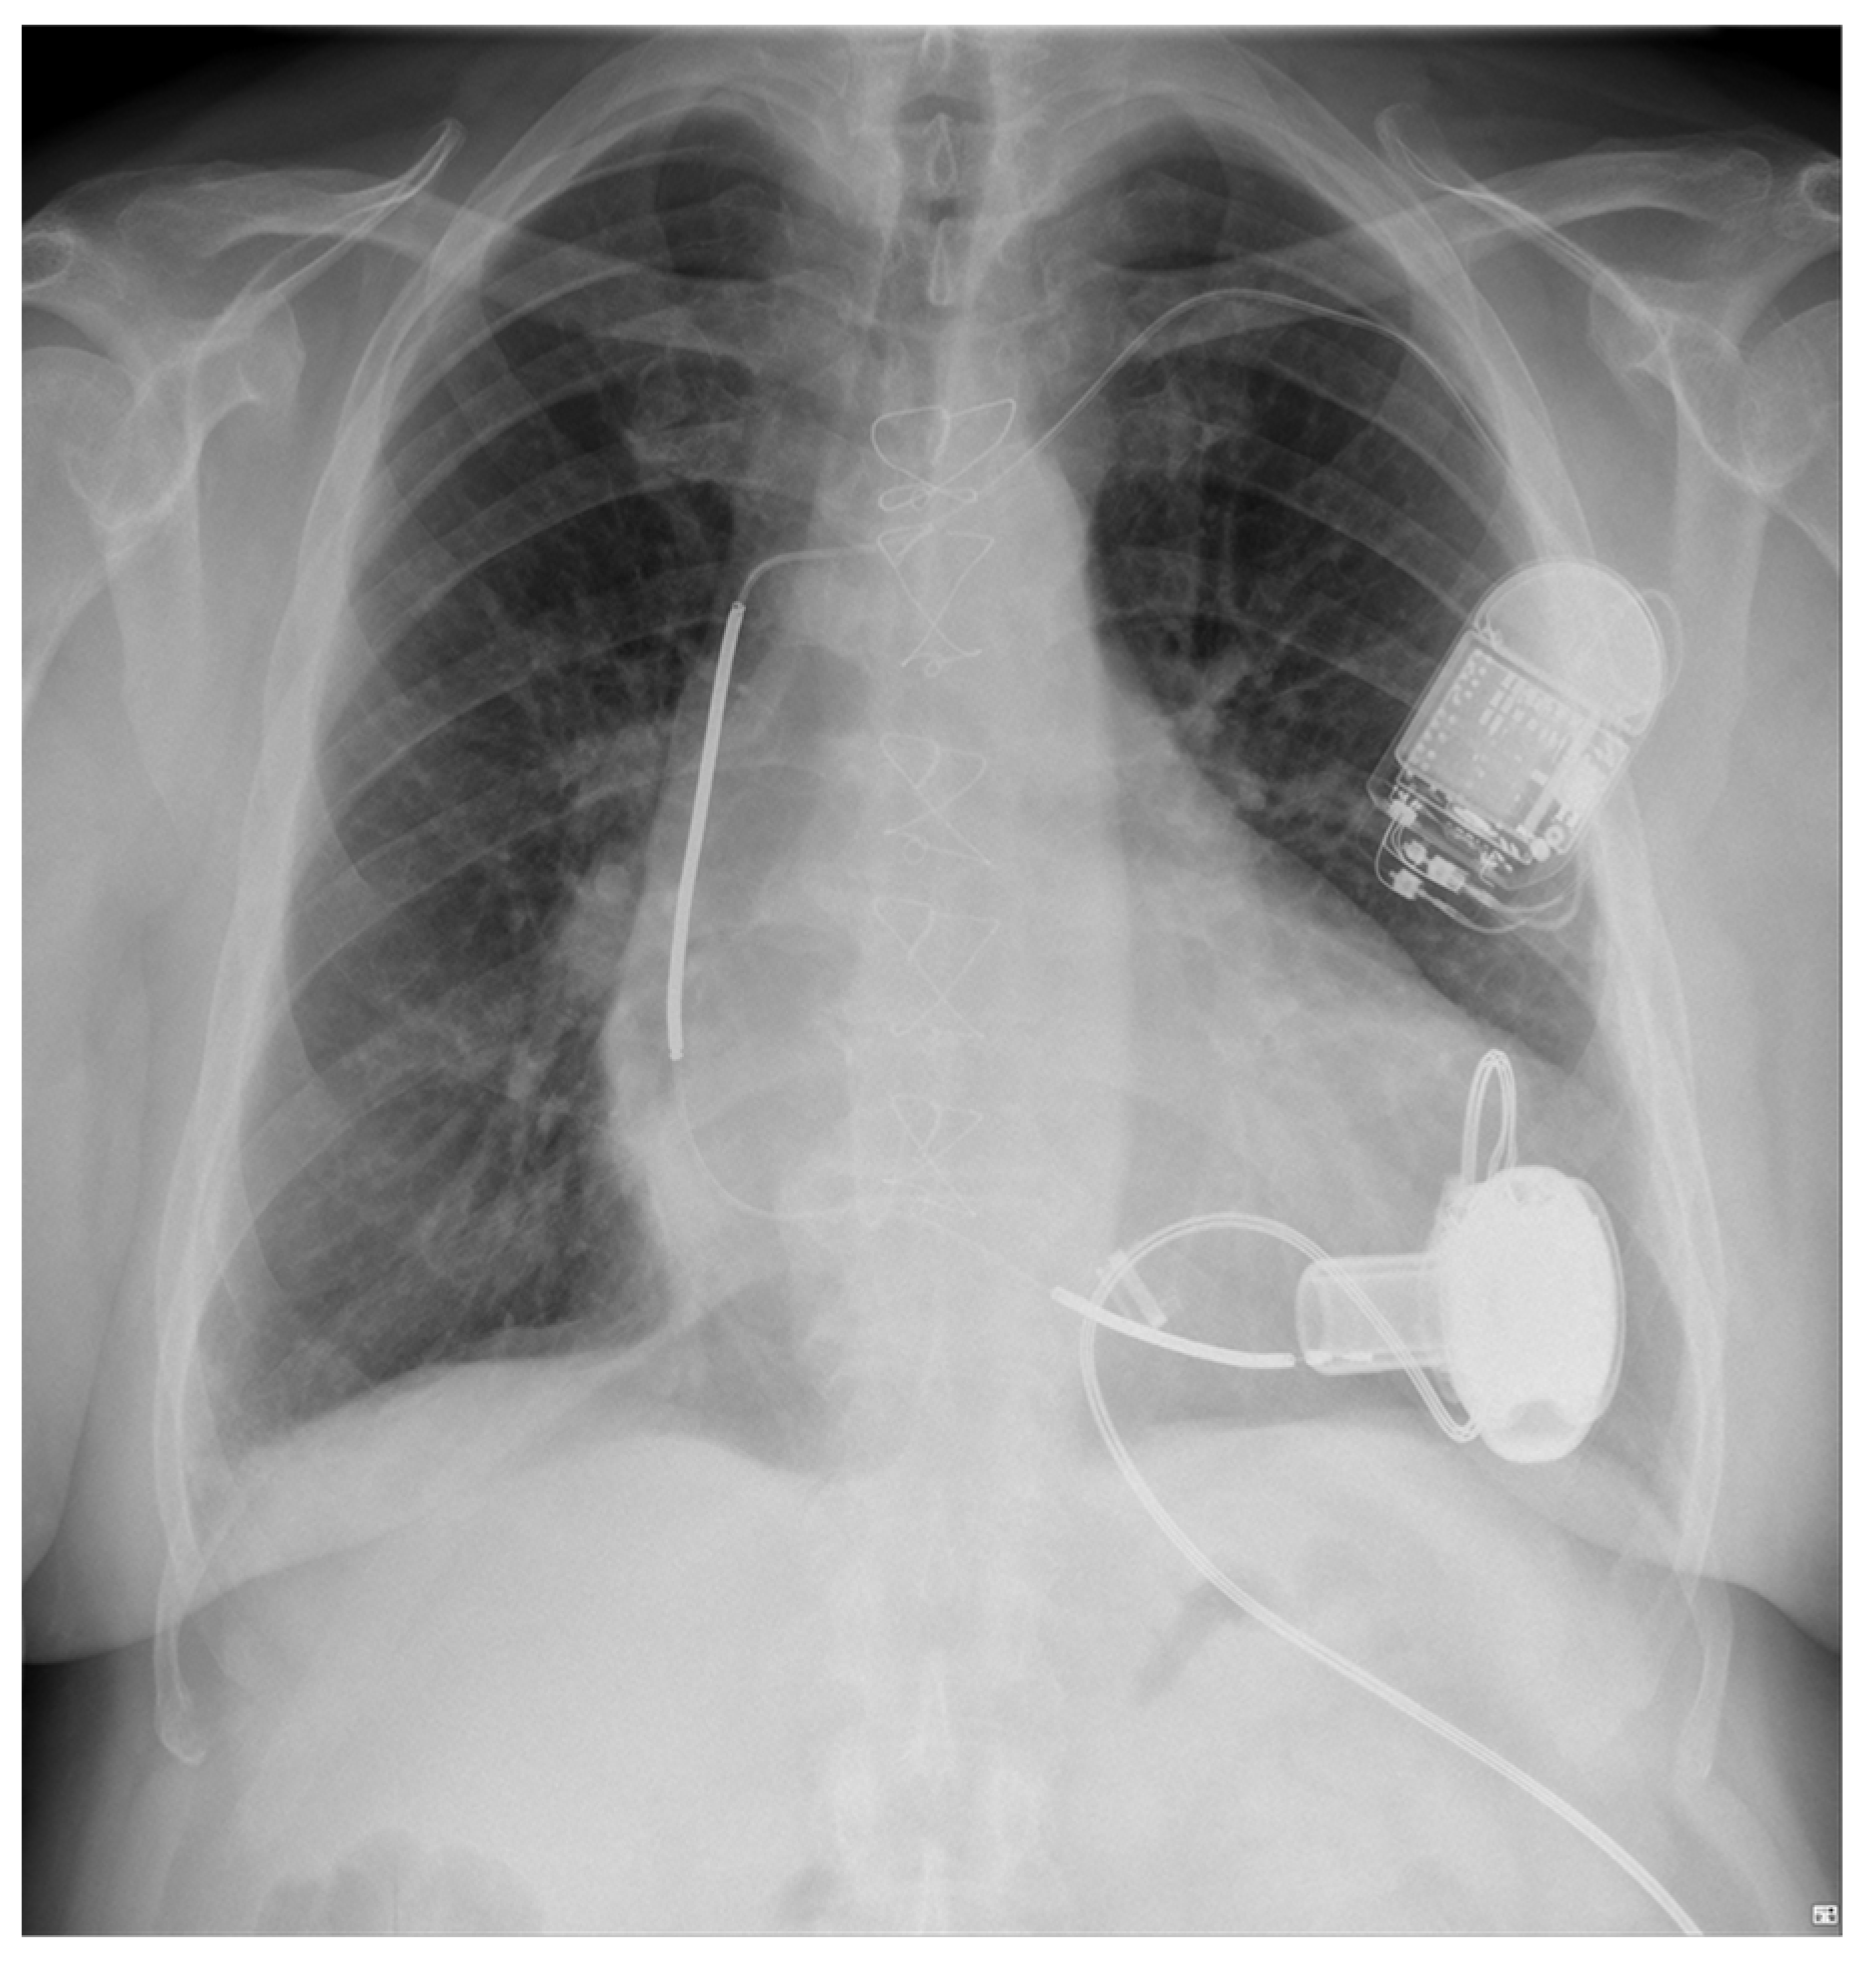

4. LVAD and Cardiac Implantable Electronic Devices